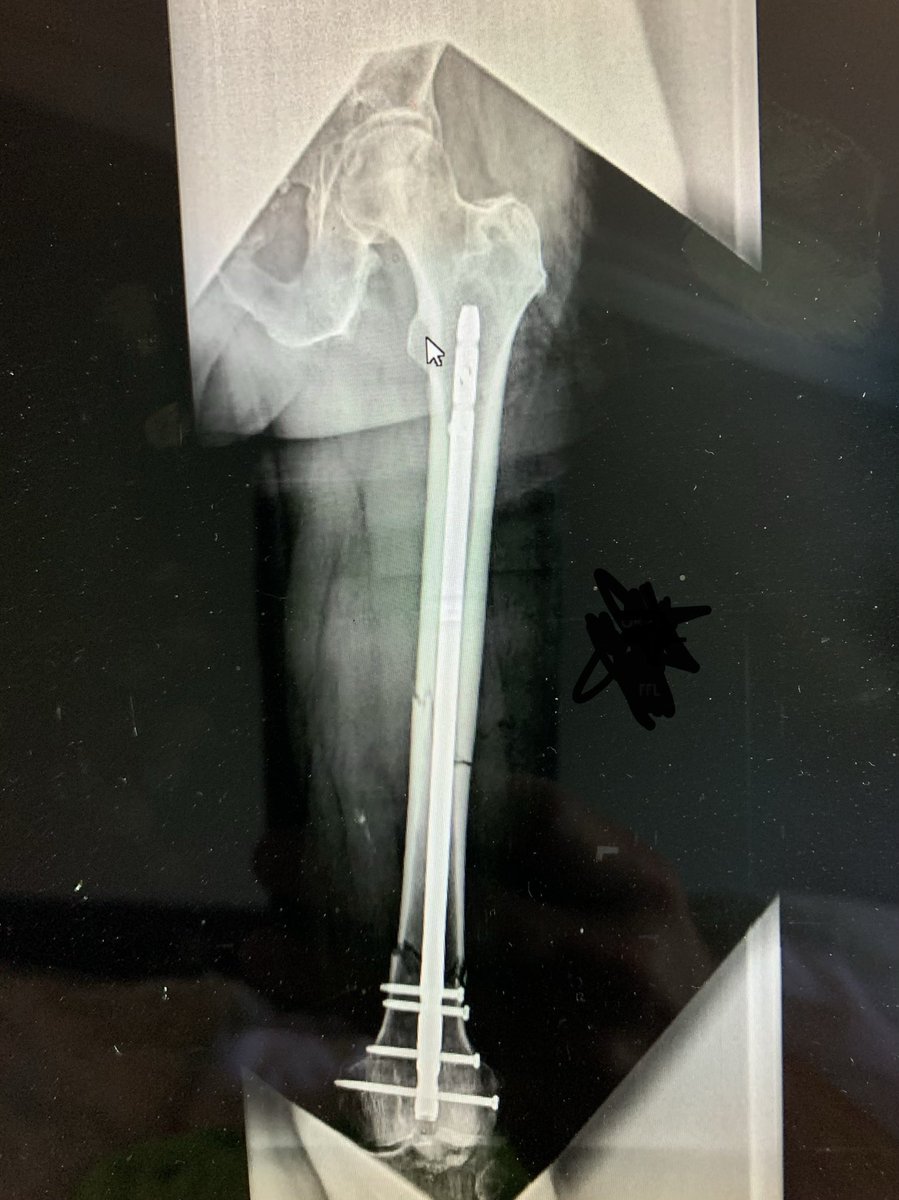

Segmental open femur fracture with ipsilateral non-displaced transverse acetabular fracture

Acetabulum managed non-op and femur treated with rIMN.

Surgeon had HIGH index of suspicion for ipsilateral femoral neck fracture.

CT negative / intra-op fluoro negative for fracture of the femoral neck

Patient returns to surg 4 weeks with femoral neck fracture

Exchange nailing for management of segmental femur w/ shorter rIMN.

Plate to bridge stress riser.